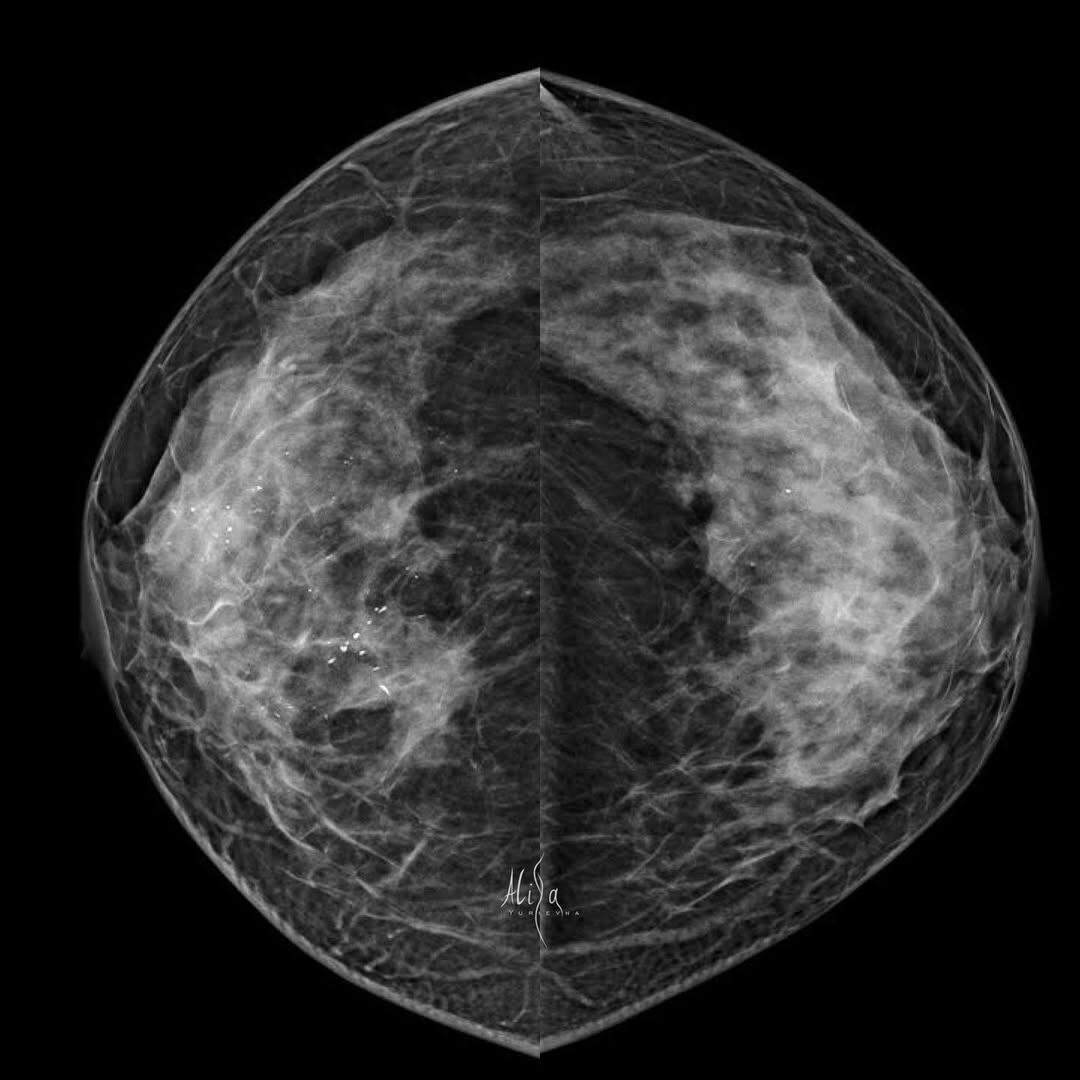

Женщина 1987гр 35 лет Или вроде ко мне вернулось оно…вдохновение. Частая история, когда привела маму на чек-ап и сама решила провериться. Странно, что раньше не замечала. Распространенный, конечно, процесс. Узлов несколько, кальцинаты на любой вкус. Ну и лу уже совсем бесструктурный. Люминальный В her2+++ Стандарт, томо, узи. Все как я люблю. #маммография #маммографияекб #привеламамуподумайосебе #маммографияспасаетжизни #диагностика #узи #томосинтез #мультимодальность #ракмолочнойжелезы

Женщина 1987гр 35 лет

Распространенный, конечно, процесс. Узлов несколько, кальцинаты на любой вкус.

Ну и лу уже совсем бесструктурный.

Люминальный В her2+++

Стандарт, томо, узи. Все как я люблю. #маммография #маммографияекб #привеламамуподумайосебе #маммографияспасаетжизни #диагностика #узи #томосинтез #мультимодальность #ракмолочнойжелезы